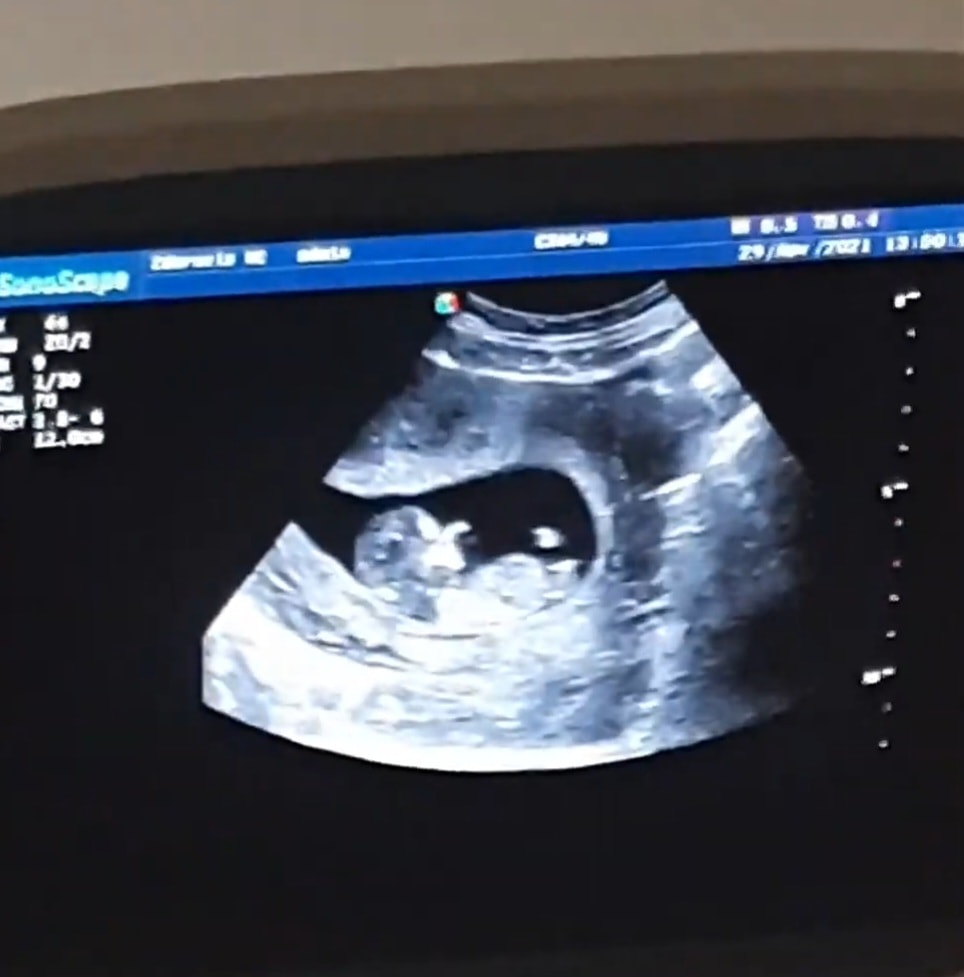

В 12 недель уже можете сдать кровь на определение Пола и все будет сразу понятно на 100 %

мне пол показывали не на таком виде. А как бы вид попы снизу. Соответственно если между ножек есть что-то, то мальчик, а если нет, то девочка. Думаю, на таком снимке ничего не разглядеть, или ошибочно можно увидеть